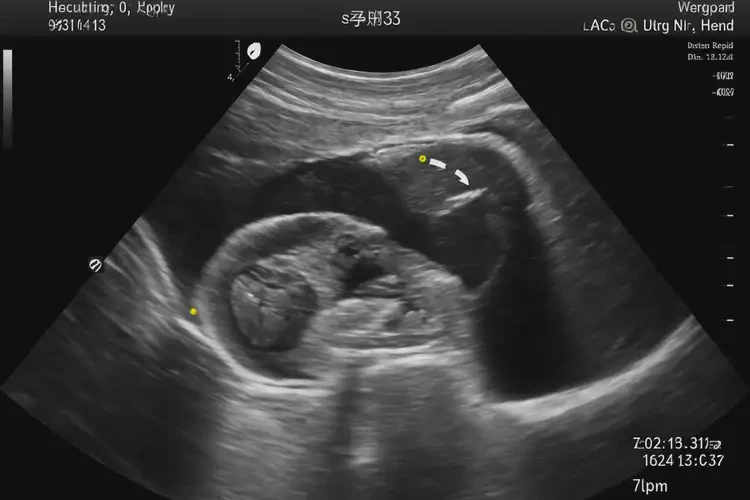

孕6周3天胎心71寶寶還能要嗎(圖1)

孕6周3天胎心71寶寶還能要嗎(圖2)

孕6周3天胎心71寶寶還能要嗎(圖3)

孕6周3天胎心71寶寶還能要嗎(圖4)